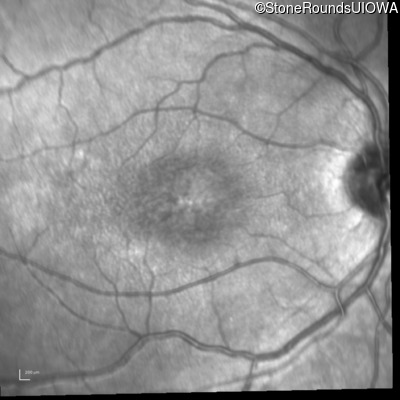

Age at visit: 11 years

This 11 year old male was never correctable to 20/20. He received glasses at age 1 for esotropia. His refraction is +4.25 +2.00 x 105 OD and +2.00 +2.00 x 80 OS.

Age at visit: 13 years

Age at visit: 15 years

Age at visit: 17 years

Age at visit: 18 years